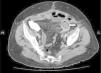

Clinical casesCase 1A 75-year-old female was admitted with a history of seven days of advancement with nausea, vomiting and abdominal pain. A month before, the patient had suffered an acute myocardial infarction and was treated with vasoactive coronary stent. The preoperative diagnosis was made by a computed tomography (TC) examination that showed an obstruction of the small intestine and a large gallstone inside of it (Fig. 1). The intraoperative findings were: dilated proximal small intestine with gallstone of 3cm diameter, impacted in the midgut. Inflammatory changes were observed in the superior right quadrant that did not allow the clear definition of the biliary anatomy or the identification of the fistulous connection with the duodenus, although it was possible to feel the gallstones in the gallbladder. The gallstone was eliminated by enterolithotomy, and a retrograde exploration of the intestine was performed without evidence of any other lithiasis at intestinal level.

Three months after surgery, the patient went to hospital with a history of 24h of vomiting and abdominal pain. The CT showed an intestinal obstruction secondary to the migration of a second lithiasis in the gallbladder.